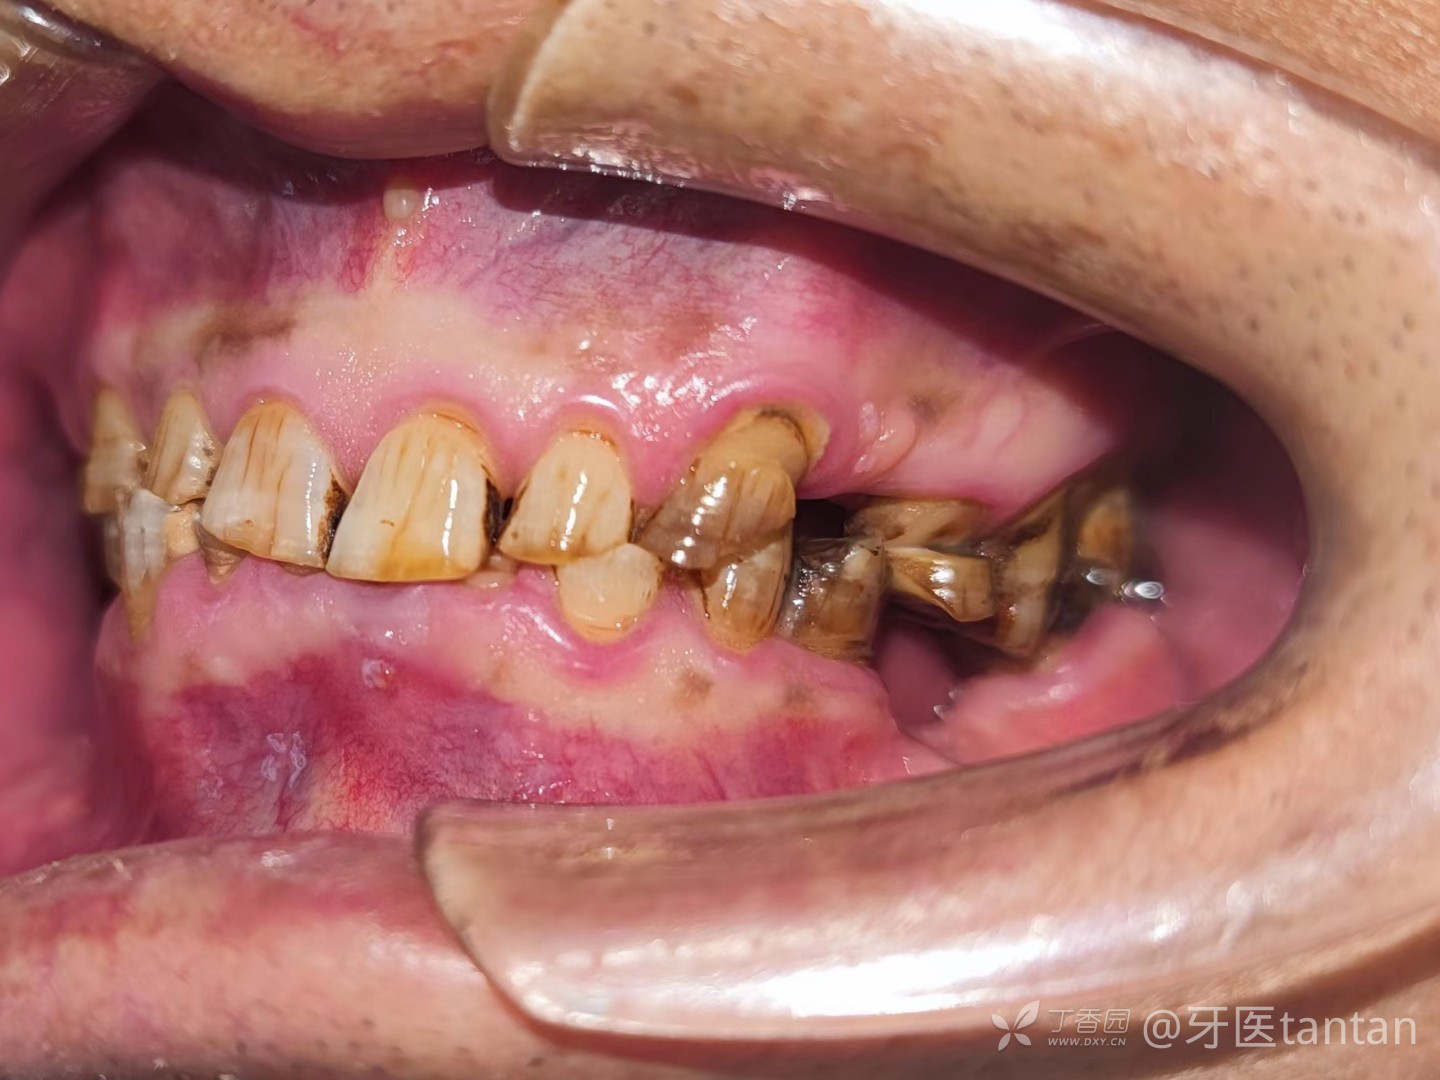

右侧咬合。

左侧咬合。